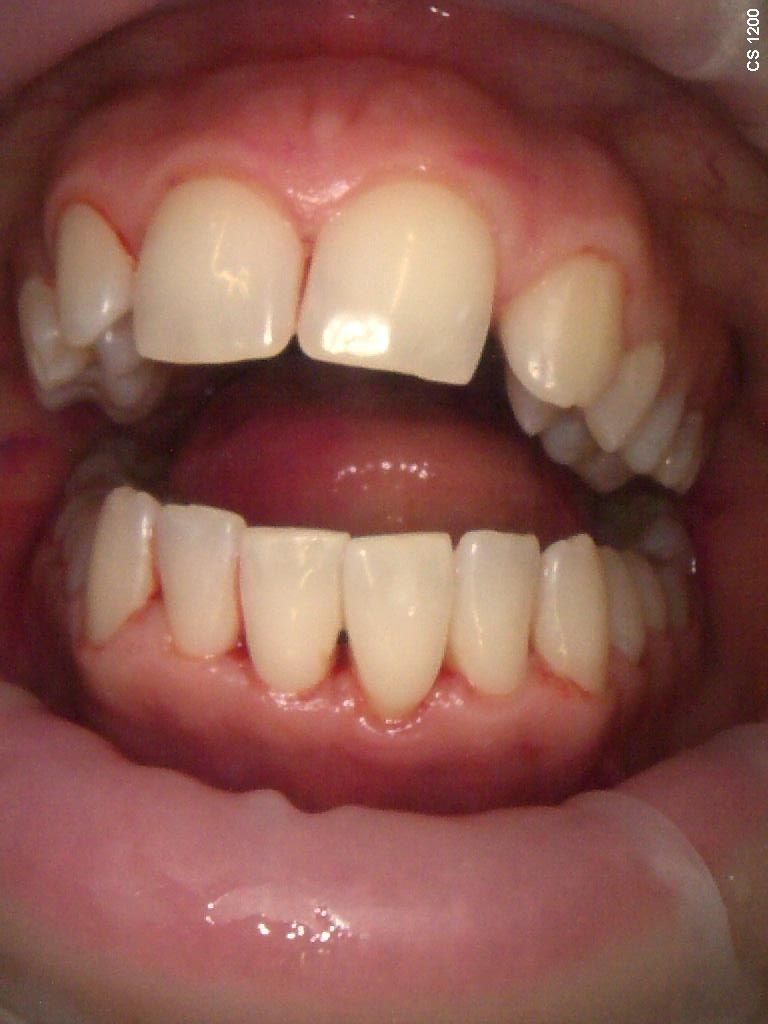

Zdjęcia i filmy